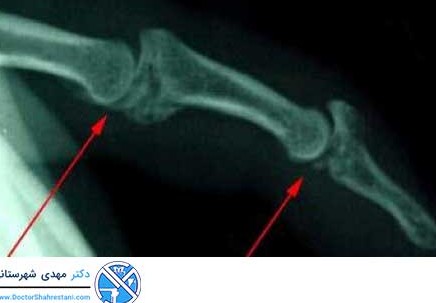

عکس ایکس ری مچ دست

تصویر برداری یکی از راه های بررسی و تعیین دقیق علت و محل برخی از بیماری ها می باشد. شایع ترین روش های تصویر برداری شامل X- Ray، CT scan و MRI می باشد.